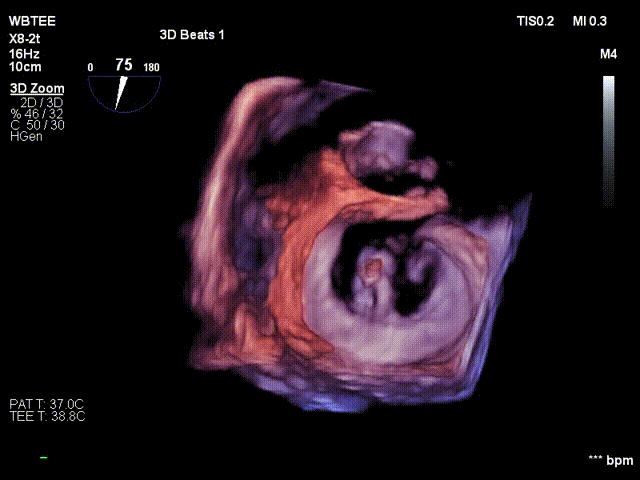

在食道超声王蓓主任的紧密配合下,经食道超声引导后傅国胜教授使用二尖瓣夹准确成功捕获前叶A2和后叶P2反流最严重区域,并予夹合,使二尖瓣在收缩期由大的单孔变成小的双孔,显著减少了二尖瓣反流。

反复测试二尖瓣钳夹的稳定性,超声复查提示二尖瓣夹内侧反流有效改善,外侧仍有部分反流,平均跨瓣压差2mmHg,肺静脉收缩期逆流频谱恢复正向,傅国胜教授团队与超声影像团队充分沟通讨论,计划在二尖瓣夹外侧再置入第二枚二尖瓣夹,遂精准释放第一个二尖瓣夹。

傅国胜教授继续在食道超声影像引导下进行高难度操作,在第一个二尖瓣夹外侧再置入第二枚二尖瓣夹NTR。

再次反复测试第二枚二尖瓣钳夹的稳定性,超声复查提示二尖瓣反流明显改善,平均跨瓣压差4mmHg。